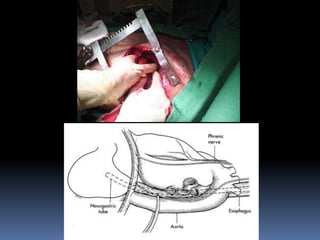

Ruptura Traumática del Diafragma

 Mas común en el lado izquierdo

 Trauma cerrado :

 lesiones radiales que posteriormente se

hernian.

 Trauma penetrante

 pequeñas perforaciones que toman tiempo en

herniarse

 Error dx al inicio por:

 Diafragma izquierdo elevado

 Dilatación gástrica aguda

 Hemoneumotórax lobulado

 Si la sospecha es alta :

 insertar SNG

 Si aparece en el HTI estudios con contrate

 Aparición de lavado peritoneal por el tubo torácico

Dx.